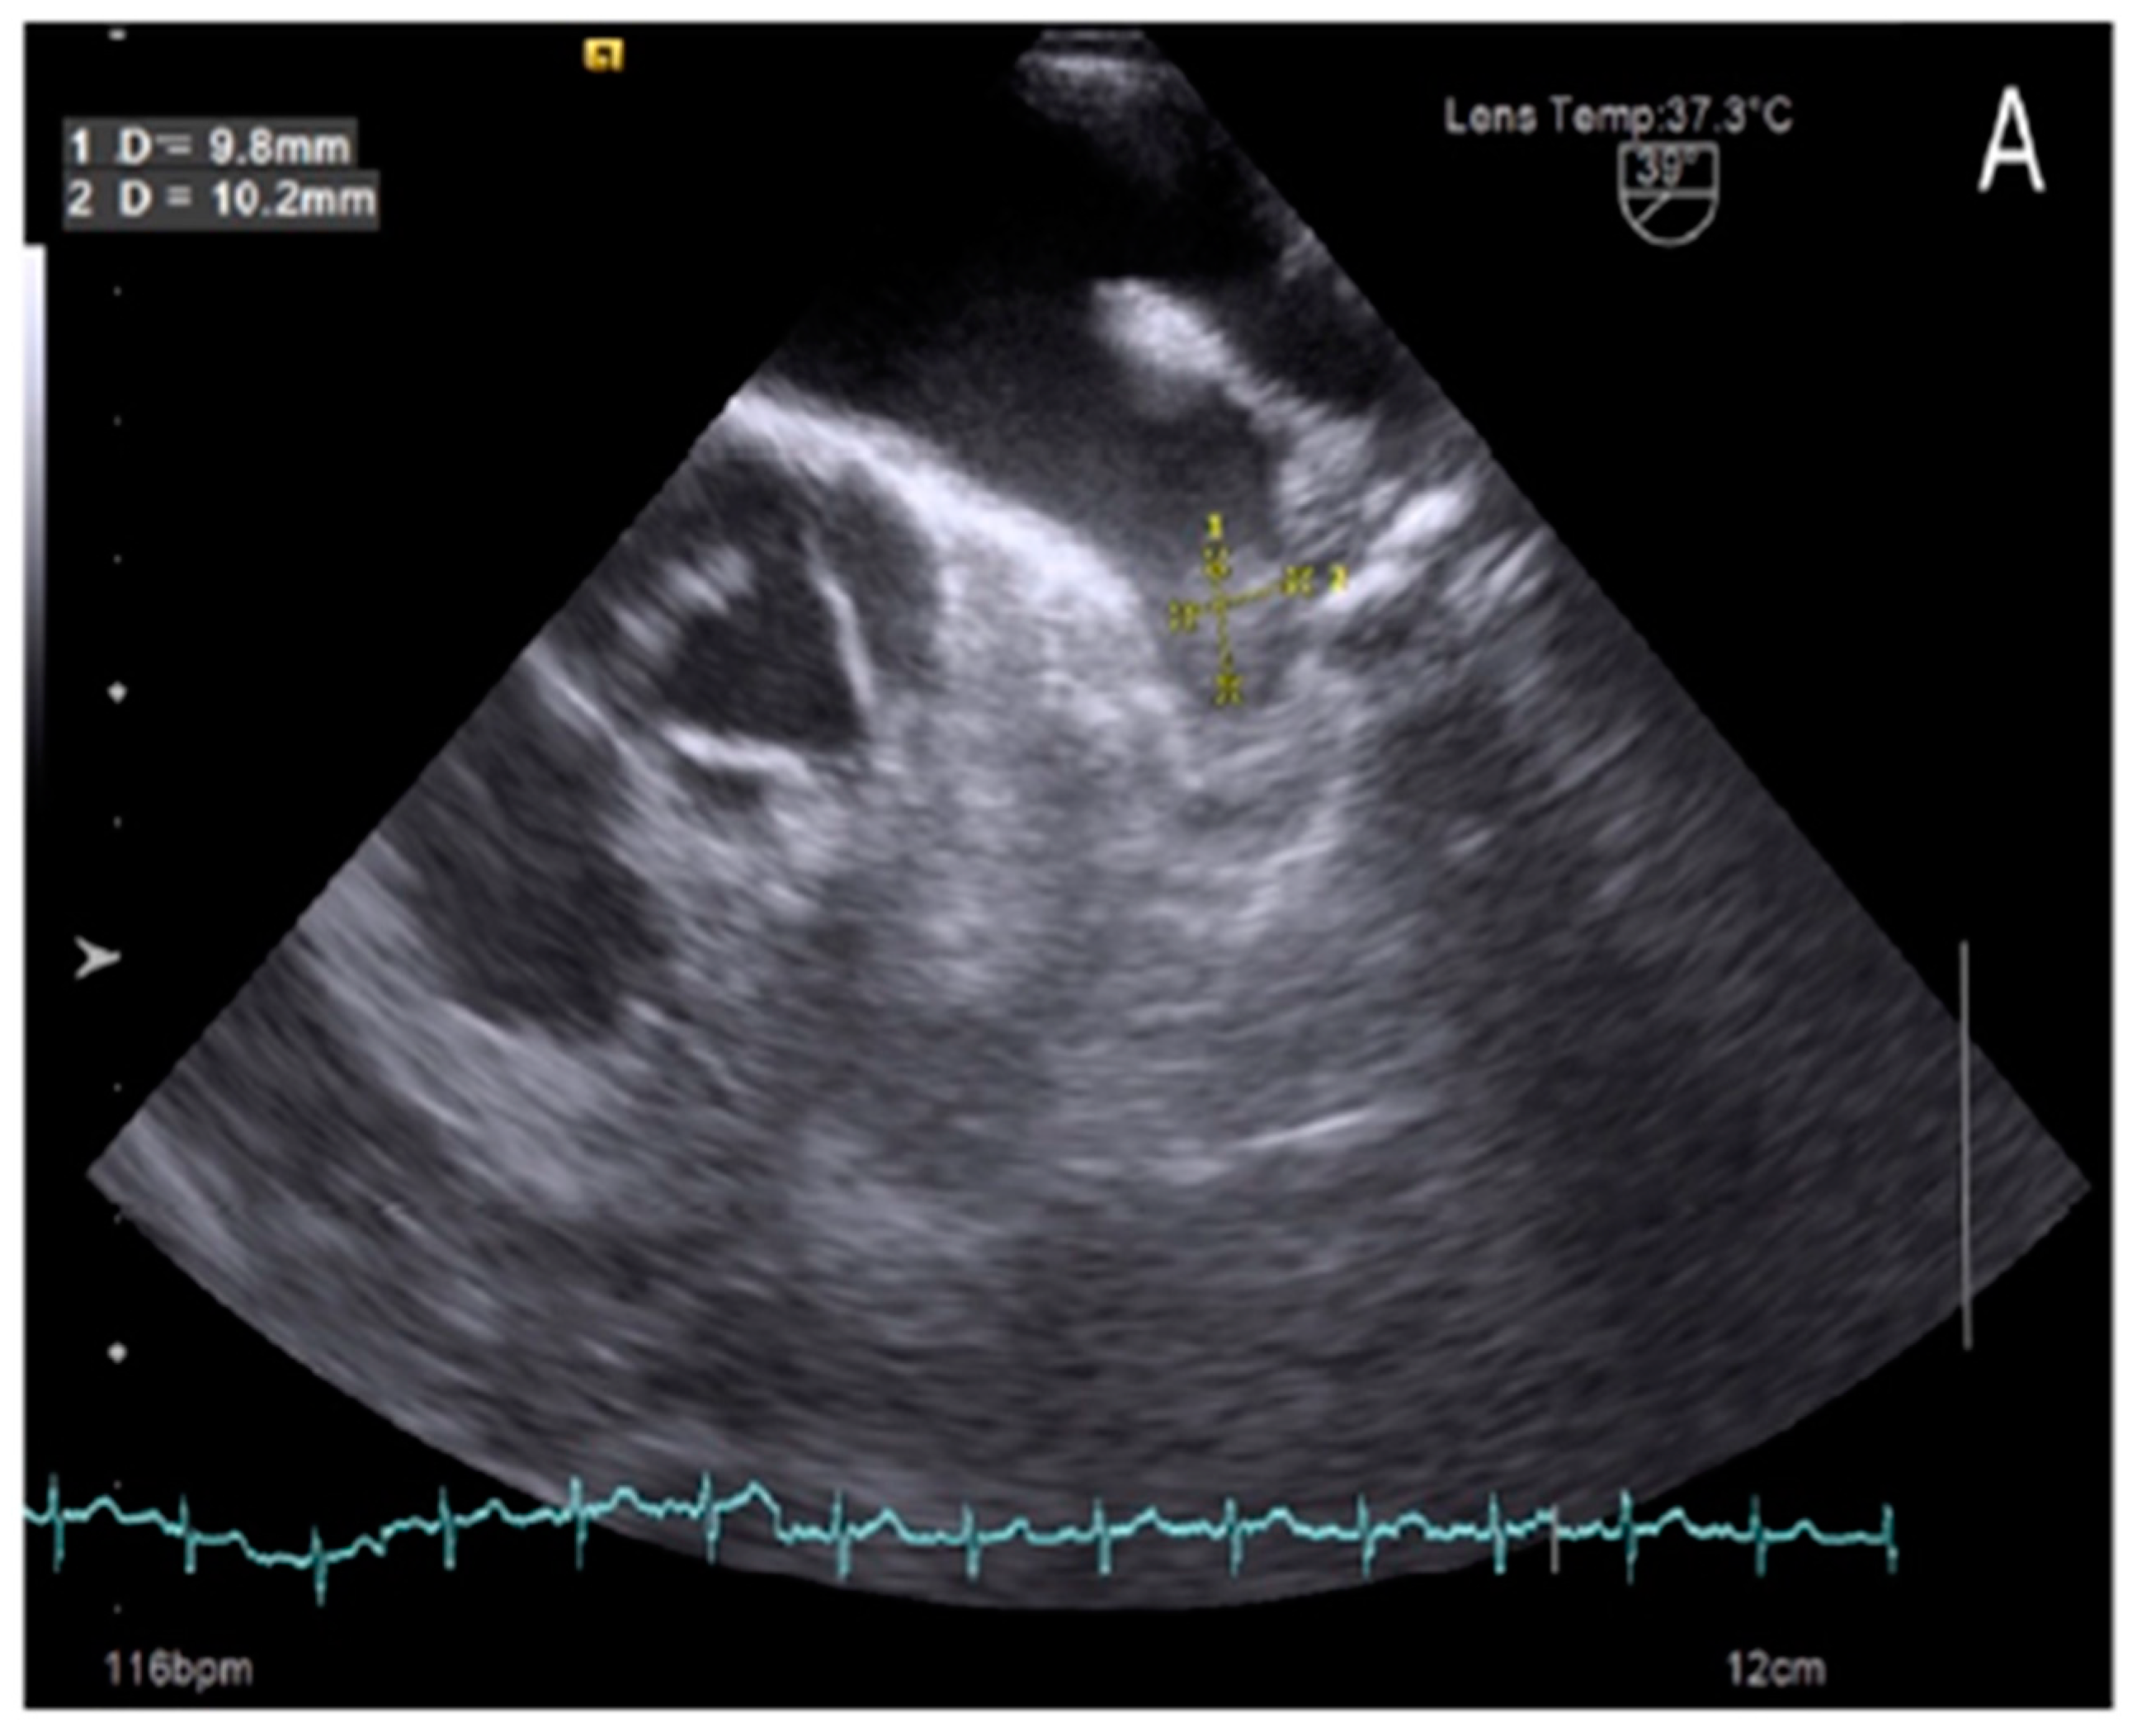

Our study also found that 7 out of 152 patients in sinus rhythm (Figure 1) had LAA thrombus, accounting for 4.6%, despite comprehensive evaluations using surface electrocardiography (ECG) and 24- to 48-hour Holter ECG monitoring. The occurrence of thrombus in patients with sinus rhythm has gained increasing attention, as recent studies suggest that LAA thrombus formation is not solely attributed to atrial fibrillation but is also influenced by other factors, such as ischemic atrial cardiomyopathy, LAA dysfunction, and LAA deformation [14,16]. These factors collectively contribute to a higher incidence of LAA thrombus in patients with sinus rhythm.

Figure 1. Left atrial appendage thrombus on transoesophageal echocardiography images in patient with sinus rhythm.